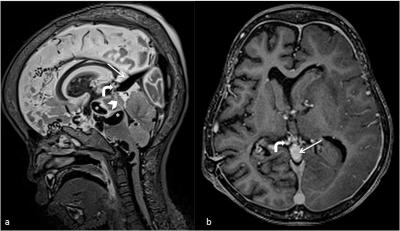

Vein of Galen Malformation

Figure 1: MRI of the brain in sagital T2WI and contrast-enhanced T1 MPRAGE demonstrate multiple serpiginous flow voids (star and bent arrow) representing dilated venous channels. Abnormal vessels (bent arrow) are seen draining into a dilated vein (thin arrow), which in turn drains into the superior sagital sinus. Narrowing of aqueduct of sylvius is marked with an arrowhead.